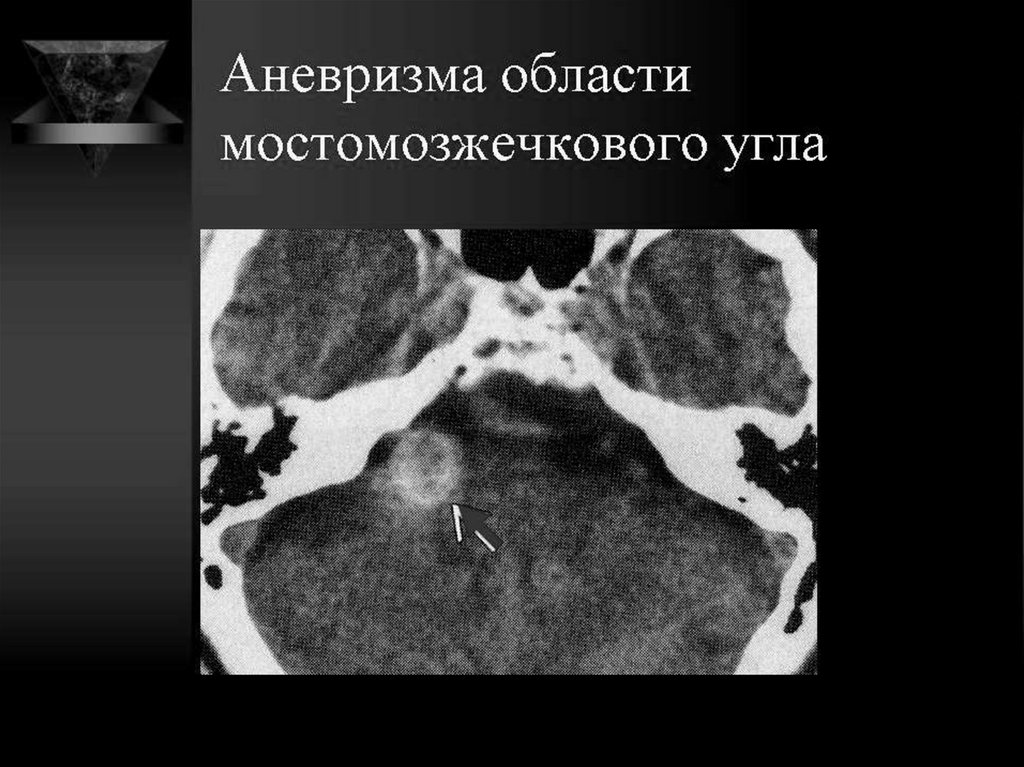

ПОРАЖЕНИЕ ВЕРХУШКИ ПИРАМИДЫ, СКАТА

АНЕВРИЗМА ВСА

Травма, инфекции –

врожденная

недостаточность

133.

134.